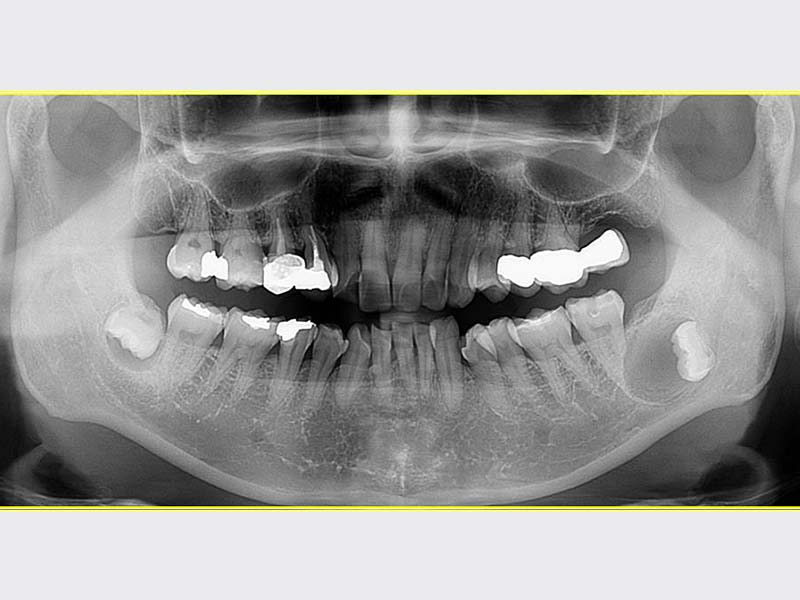

智齒手術

• 智齒手術